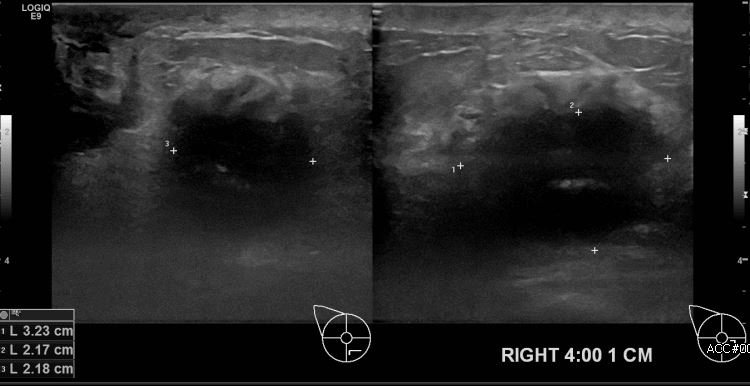

상기환자 우측 유방에 멍울로 내원하신 40대 여성분으로 본원 초음파상 우측 4시 방향

에 1cm 떨어진 거리의 멍울 조직검사 시행하여 우측 침윤성 유관암 진단 되었습니다.